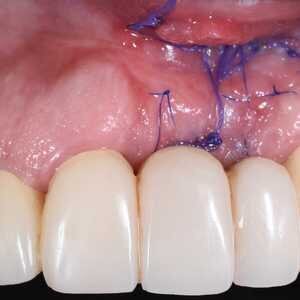

Dans cet article, nous présentons un cas clinique qui montre comment une mauvaise mise en place d'un implant peut rendre impossible la réhabilitation prothétique, ce qui nécessite une nouvelle planification chirurgicale et de réhabilitation pour obtenir l'esthétique souhaitée. Le patient se présente à notre observation avec une réhabilitation prothétique incongrue, avec bride en résine, support dentaire et implantaire, avec la présence d'un implant en position 2.1 vestibulaire et avec l'émergence dans le fornix, dans la mucosa alvéolaire. L'évaluation de la tomodensitométrie montre la position incorrecte de l'implant et la perte constante dans le sens transversal de la structure osseuse (Figs. 1, 2). Par conséquent, le plan de traitement suivant a été choisi : retrait de l'implant et préparation prothétique de l'élément 2.3, fabrication d'un premier support dentaire temporaire pour guider la cicatrisation des tissus (Figs. 3-7). Après 4 mois, une greffe d'épithélium conjonctif libre est réalisée avec ablation du palais pour compenser l'espace transversal des tissus mous, puis le provisoire est remodelé afin de faciliter la cicatrisation des tissus (Figures 8-11). Après 9 mois de maturation des tissus, la finalisation prothétique fixe avec support dentaire est réalisée (Figs. 12-14).

L'examen clinique ne se limite donc pas à l'étude des modèles montés dans l'articulateur, le wax-up diagnostique, les images radiographiques (OPT, TAC) et l'utilisation de guides chirurgicaux sont importants. Jusqu'à récemment, le retrait d'un implant entraînait une perte importante de tissu osseux et la nécessité de procéder à une greffe osseuse. Cependant, les progrès technologiques ont conduit à la mise au point d'outils qui facilitent le retrait des implants par des procédures simples et conservatrices. Les greffes de gencive libre pour augmenter la bande de tissu kératinisée ont été décrites pour la première fois dans la littérature parodontale en 1963 par Bjorn et en 1966 par Nabers. Le site idéal pour le prélèvement se situe au niveau du palais dur entre la partie adipeuse et la partie riche en tissu glandulaire, approximativement dans la zone prémolaire. L'immobilisation du greffon est une condition nécessaire à la survie du greffon, et il est également essentiel qu'il y ait un contact intime entre le greffon et le lit receveur, car l'interposition séreuse interrompt le soutien nutritionnel et cause la nécrose du greffon.